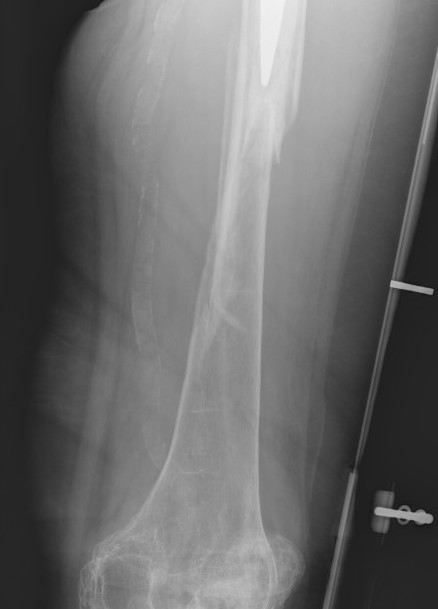

Type C: Fracture distal to tip of stem

Management

ORIF Locking cable plate +/- cortical strut allograft

- overlap femoral implant

- to distal femur